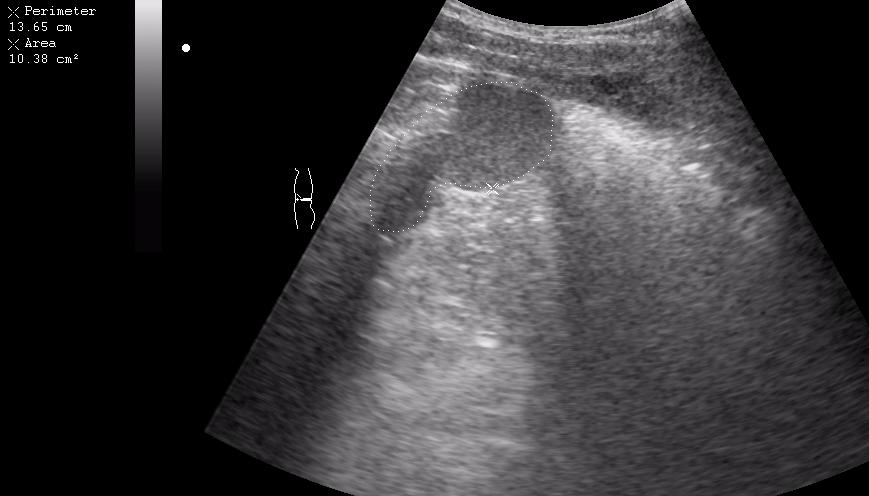

Девочка-подросток поступила в приемное отделение с жалобами на боли в эпигастральной области. На животе - рубец после срединной лапоротомии - полгода назад оперирована по поводу травмы и разрыва селезенки, со слов мамы - выполнена спленэктомия.

При УЗИ в эпигастральной области обнаружилось такое образование.

что-то в сальнике, но не инородное тело. может быть ошметок селезенки (аутотрансплантат)? васкуляризация есть?

Да, действительно, это аутотрансплантат ткани селезенки в большой сальник.